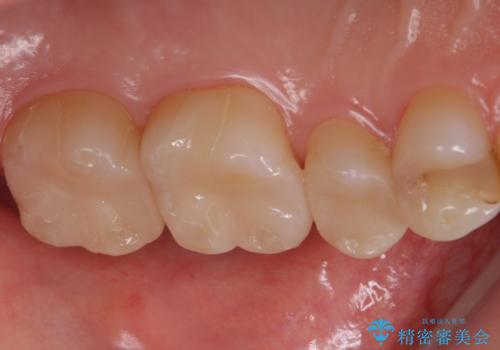

- 左上567 セラミックインレー:77,000円×3本費用は治療当時の料金となります

銀の詰め物と不適合な詰め物を精度の良いセラミックインレーに変えることができました。